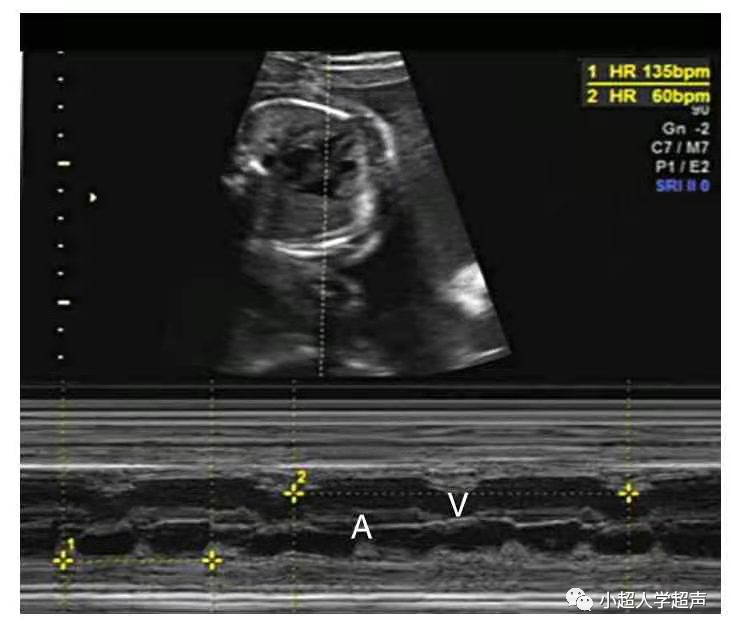

正常M型超声心房波起始部至心室波起始部间距或频谱多普勒A-V间距(相当心电图P-R间期)<150ms

(1)一度房室传导阻滞

指房室传导时间延长,超过正常范围(150ms),但每个心房激动仍能传入心室。

一度房室传导阻滞频谱多普勒A-V间距>150ms(取样容积可左室流入-流出道区,上腔静脉和升主动脉相邻区,下腔静脉和腹主动脉相邻区,肺动、静脉相邻区--动脉代表室率)